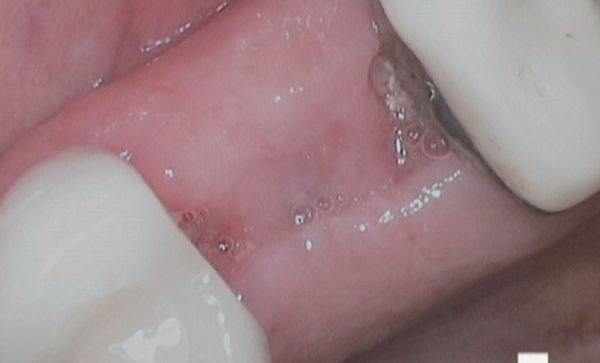

Case 47